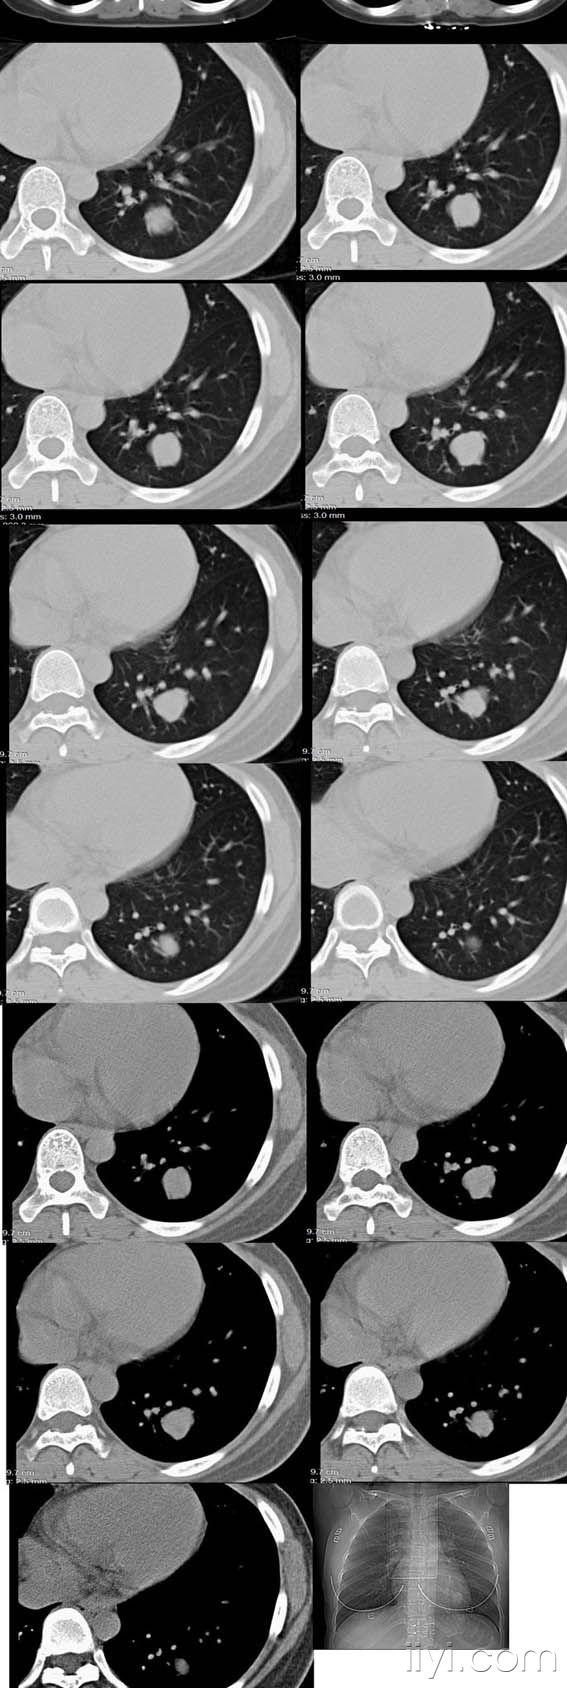

【读片】21岁女孩,胸部结节,请您会诊,结果正在随访中.

左肺上叶尖后段磨玻璃结节严重吗胸外科